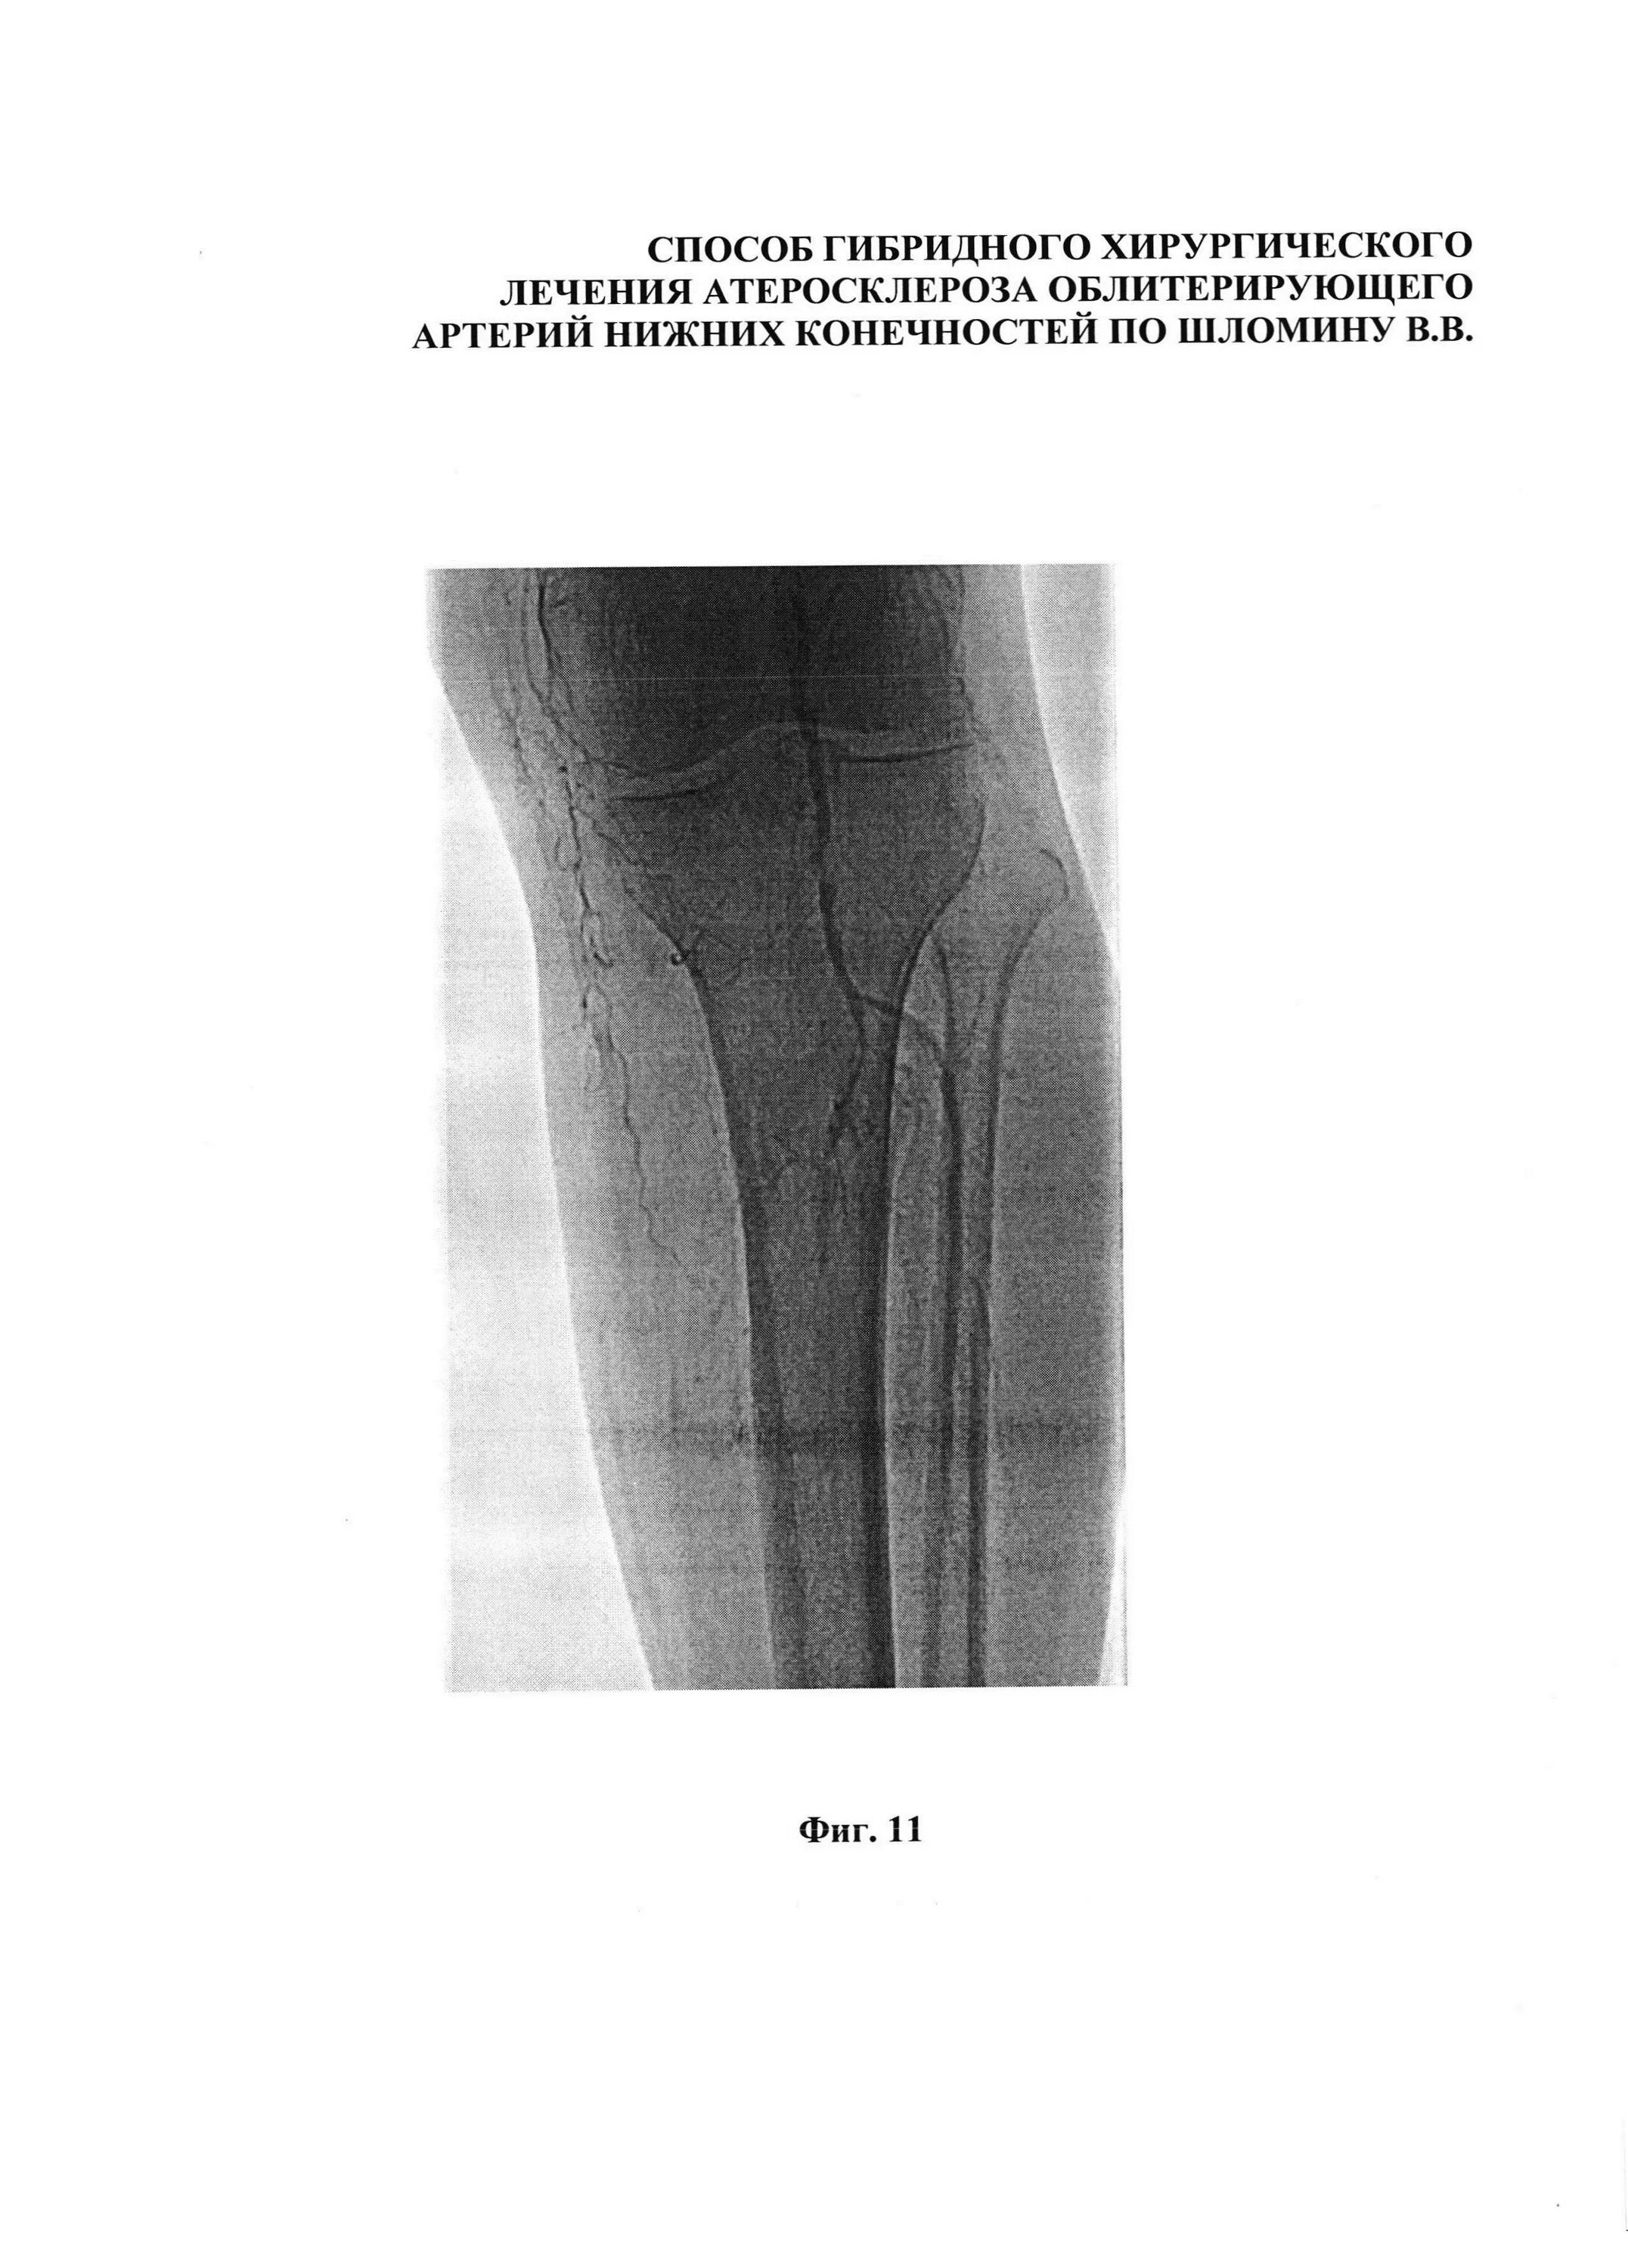

Облитерирующий атеросклероз нижних конечностей код мкб